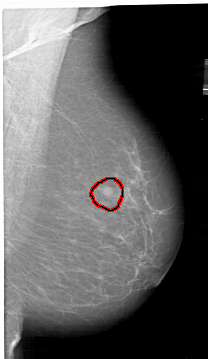

A_1409_1.RIGHT_CC

RIGHT_CC LINES 6766 PIXELS_PER_LINE 3541 BITS_PER_PIXEL 12 RESOLUTION 43.5 OVERLAY

FILE: A_1409_1.RIGHT_CC.OVERLAY

TOTAL_ABNORMALITIES 1

ABNORMALITY 1

LESION_TYPE MASS SHAPE ROUND MARGINS ILL_DEFINED

ASSESSMENT 4

SUBTLETY 4

PATHOLOGY BENIGN

TOTAL_OUTLINES 1

BOUNDARY